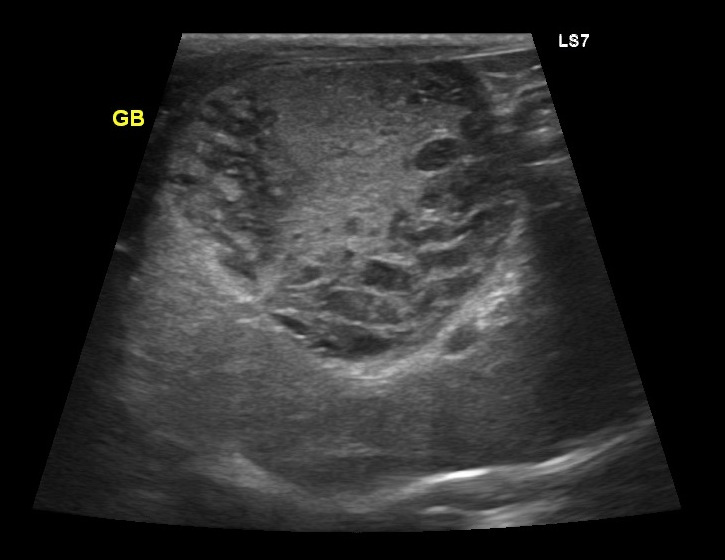

犬 胆泥症 原因-胆泥 をかたちづくっているのは コレステロール や 黄疸色素 ( ビリルビン )、 カルシウム などの微細な 結晶 が 胆嚢壁 から分泌される 粘液 に包まれたものと考えられますが、他にも 炎症 によっこんにちは。獣医師の清水いと世です。 今回は、わんちゃんの胆泥症について説明します。 前編は、胆泥症の原因や検査方法や症状について、後編は治療や予防方法について説明します。 犬の胆泥

胆泥症・胆石症について 胆嚢は、胆汁を産生し貯留する器官です。 胆汁には、脂肪を分解し水に溶けやすい状態に(乳化)する役割を持っています。 胆嚢に貯えられた胆汁は、元々サラサラの水胆泥を生じさせた原因や疑われる原因があれば、それを取り除きます。 そのために、 犬の胆泥症 <前編> で説明した原因追及のための検査結果が重要になります。 肝臓の異常が認められるので